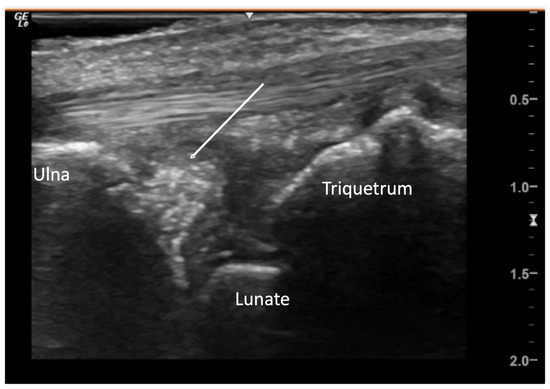

2.6. Calcium Deposition

4.2.3. Ulnar Aspect